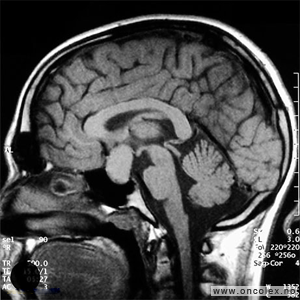

Bildediagnostiske undersøkelser

MR er det viktigste diagnostiske hjelpemiddel for å påvise hjernesvulster. Ofte gjøres det først en CT av hjernen, men CT-undersøkelsen har klare begrensninger når det gjelder fremstilling av hjernesvulster. CT- eller MR-angiografi gjøres av og til for å kartlegge blodåresystemet i hjernen og eventuelle blodårer i og rundt en svulst.

Undersøkelse og kartlegging av aktiviteten i hjernen og områder som styrer de ulike hjernefunksjoner (funksjonell MR), er et viktig supplement i utredningen før operasjon. Dette gjelder spesielt for svulster som ligger i nærheten av områder som styrer språk og motorikk (bevegelse). Måling av hjernens elektriske aktivitet (EEG) og testing for språkfunksjonen i de to hjernehalvdelene (WADA-test) kan også være aktuelt.